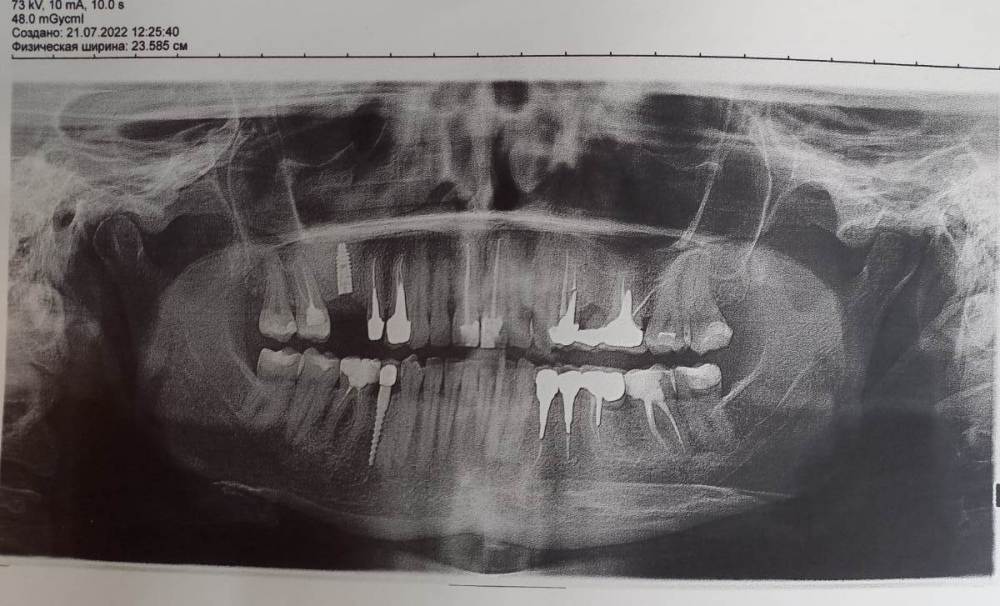

Elena20 Опубликовано 21 июля, 2022 Автор Поделиться Опубликовано 21 июля, 2022 08.07.2022 в 18:35, Irouil сказал: Обычно винты-заглушки сделаны из того же материала, из которого сделаны импланты. Очень маловероятно, что это названный Вами сплав, но я не берусь утверждать на 100% С другой стороны, скорее всего титановое основание Вашей коронки на другом импланте как раз из этого сплава. Ушитый имплант никак не должен воздействовать со средой полости рта, включая материалы других конструкций и реставраций Нужны снимки Здравствуйте, сделала снимок, посмотрите, пожалуйста. Ссылка на комментарий

Irouil Опубликовано 21 июля, 2022 Поделиться Опубликовано 21 июля, 2022 @Elena20 судя по предоставленной рентгенограмме, Ваш имплант в позиции 1.6 зуба установлен строго по протоколу, винт-заглушка фиксирован плотно. Одновременно с этим, насколько я вижу, Вам был проведён синус лифт, надо понимать какой именно графт (наполнитель) использовался, некоторые их них могут быть аллергенами, хотя навряд могут вызывать металлический привкус в полости рта. Кроме того, сам факт наличия описанного временного лага между имплантацией и появлением симптомов говорит не в пользу подозрений в сторону импланта. Я бы действительно начал с соседнего зуба, 1.5. Вкладка там непокрыта и может быть причиной Ваших жалоб Ссылка на комментарий

Elena20 Опубликовано 22 июля, 2022 Автор Поделиться Опубликовано 22 июля, 2022 (изменено) 9 часов назад, Irouil сказал: @Elena20 судя по предоставленной рентгенограмме, Ваш имплант в позиции 1.6 зуба установлен строго по протоколу, винт-заглушка фиксирован плотно. Одновременно с этим, насколько я вижу, Вам был проведён синус лифт, надо понимать какой именно графт (наполнитель) использовался, некоторые их них могут быть аллергенами, хотя навряд могут вызывать металлический привкус в полости рта. Кроме того, сам факт наличия описанного временного лага между имплантацией и появлением симптомов говорит не в пользу подозрений в сторону импланта. Я бы действительно начал с соседнего зуба, 1.5. Вкладка там непокрыта и может быть причиной Ваших жалоб Спасибо большое за ответ! Именно на удалении вкладки 1-5 я и настаиваю, но мой доктор отказал мне, мотивируя тем, что не видит в этом смысла. Но он изначально мыслит в другом направлении, так как считает, что титан в принципе не может давать гальваническую активность. Поэтому, не отрицая самого гальванизма, он не видит его в зоне импланта, а предлагает искать в других зубах. А в этом ни вижу смысла я. Лично я вижу образование гальванической пары именно между имплантом и вкладкой 1-5. При этом имплант выступает катодом, а вкладка анодом, результат - гальваническая коррозия вкладки, что и подтверждается сильным кисло-металлическим вкусом от вкладки. Вкладка сейчас закрыта пластмассовой коронкой временной, но от этого не легче. Жжение очень сильное в районе двух единиц 1-5 и 1-6, просто огнем горит, ночью уже не сплю, не знаю куда себя девать, причем ощущение такое, что токи жгут не по поверхности десны, а как-будто изнутри десны. Небольшое уточнение: у вкладки есть участок контакта с десной, так как зуб ушел под коронку в результате облома стенки немного глубже десны. Таким образом, мы имеем контакт и импланта с десной в зоне заглушки и контакт вкладки с десной. Десна выступает в роли проводника. Так как доктор отказал в удалении вкладки, единственное, что у меня остается, дождаться установки индивидуального циркониевого абатмента и тем самым получить изоляцию импланта от десны. Но самое страшное в таком варианте то, что мне придется пройти ужас, который начнется после установки формирователя из сплава Ti6Al4V. Как я переживу этот период, не представляю. В связи с этим у меня возникает ряд вопросов. Разорвется ли в момент установки циркониевого абатмента гальваническая пара? если да, то тогда вкладку можно не убирать? Если вкладку оставить, сохранится ли ее качество, учитывая, что она начала коррозировать? этой вкладке 12 лет. Закрывать ее планируется цирконом Если вкладку убирать (и соответственно искать другого доктора), то что поставить на замену? мой доктор сказал, что циркониевые вкладки очень хрупкие и ломаются. Предлагает заизолировать вкладку глубоко под десну цирконом. На имплант разумеется тоже циркон. Для того, чтобы протестировать как сработает установка абатмента, сколько времени допустимо ходить с абатментом без коронки? или нужно сразу закрывать коронкой? Изменено 22 июля, 2022 пользователем Elena20 Ссылка на комментарий